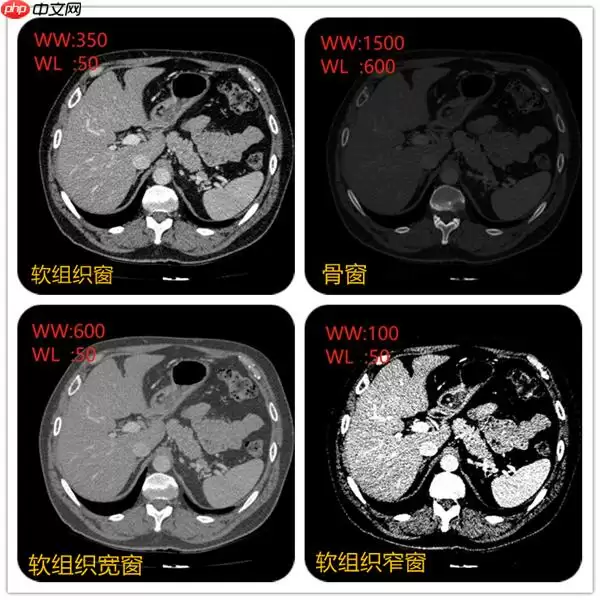

"不同窗宽窗位对CT图像显示的影像"

在上面视频可以看到不同窗宽窗位,图像显示不一样。例如当窗宽350,窗位50左右的时候,肝脏、脾脏等软组织密度和对比度都比较合适。当窗宽1600,窗位600左右的时候,肋骨、椎体等骨质的组织的密度和对比度看起来比较合适。不同的组织的CT值可以当成一个固有属性。例如肝脏在50~ 70Hu,脾脏50~ 65Hu等。

例如窗位选择50, 窗宽选择350,图像中可以显示的CT值范围就是(窗位-窗宽/2)至(窗位+窗宽/2)即-140~225,图像显示的时候只要CT值低于-140的组织都会显示黑色。CT值高于255都会显示白色。所以肝的CT值约50,要肝脏对比度显示的好,就先把窗位定在50,在选择窗宽。窗宽约大显示组织密度差别较大的结构,窗宽越窄,组织对比度强,显示密度差别较小的结构。

所以不同的窗宽窗位非常影响诊断医生的判断。例如右上角采用骨窗后对骨质是否有病变有一个很好的诊断。